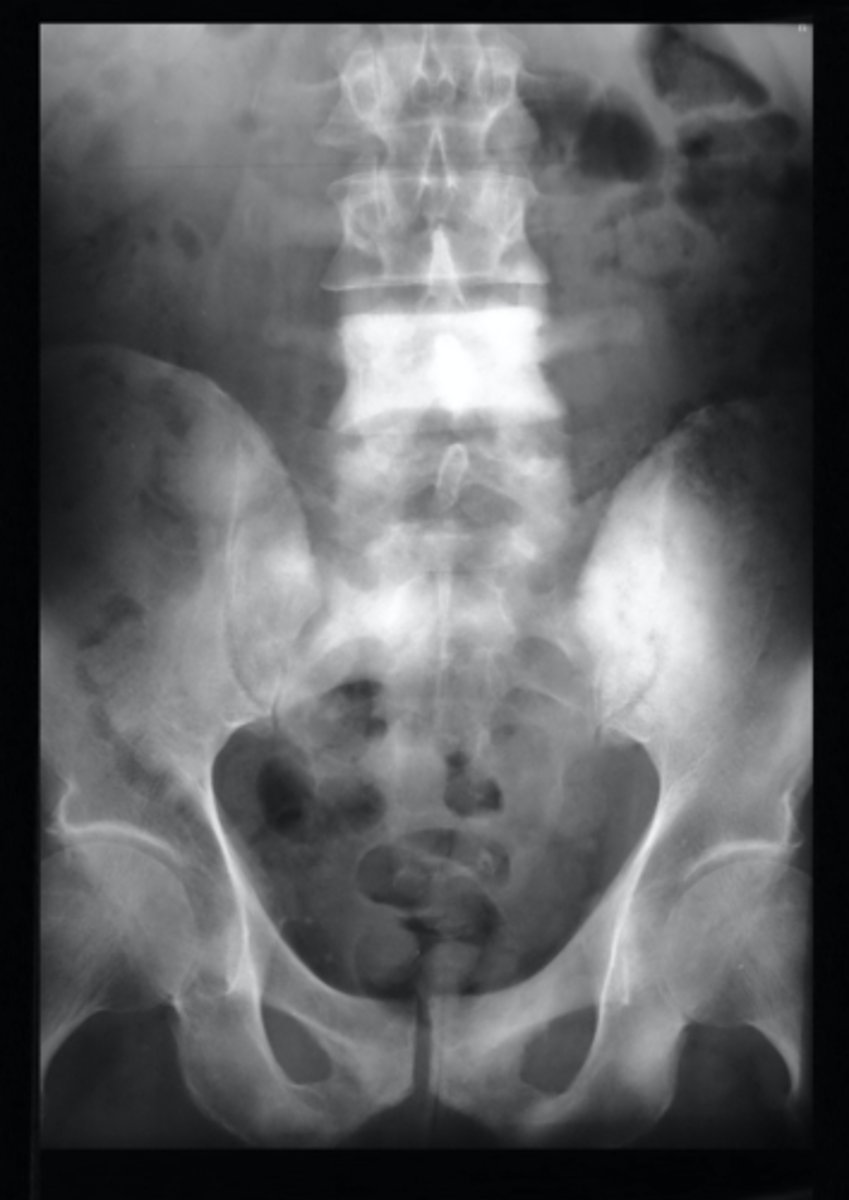

Vignette #1:

Sex: Male

Age: 62

Chief Complaint: Patient presents with low back pain and initiating urinary streams. He reports polyuria in the middle of the night.

Objective Findings: Kemps + Diagnostic Imaging: X-ray

Which labs would you expect to be positive? (Choose 3)

a. PSA

b. Acid phosphatase

c. Alkaline phosphatase

d. ESR

e. CRP

f. Proteinuria

g. BUN

h. Biopsy for Reed Sternberg

What are your differential diagnoses? (Choose 3)

a. Paget's

b. BPH

c. Osteomyelitis

d. Multiple Myeloma

e. Blastic Metastasis

f. Hodgkin's Disease

g. Lytic Metastasis